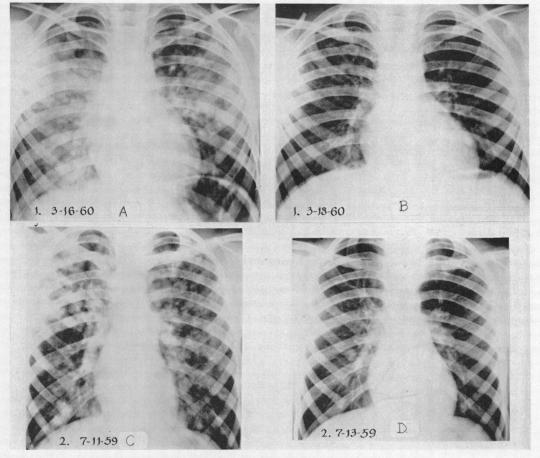

Further studies of high altitude pulmonary oedema.

Br Heart J. 1962 Jan;24(1):95-102. doi: 10.1136/hrt.24.1.95.